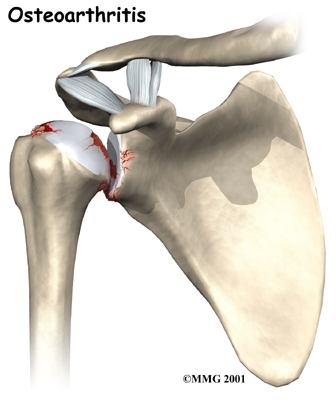

The most common reason for undergoing shoulder replacement surgery is osteoarthritis. Osteoarthritis is caused by the degeneration of the joint over time, through wear and tear. Being that the shoulder is not a weight-bearing joint, it does not suffer as much wear and tear as other joints such as the weight-bearing hip and knee joints. Although osteoarthritis in the shoulder can occur without any causative injury to the shoulder, this is uncommon; usually it is a subsequent result of another injury or disease in the shoulder joint.